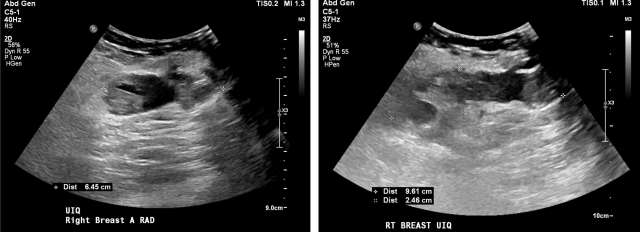

• US:  Anechoic simple fluid collections. Complicated fluid collections with heterogenous echogenicity are also possible, Figure 4.17

Case: Post-Surgical Fluid Collections Figure 4

Figure 4 - Homogenous hypoechoic fluid collection with internal debris, compatible with seroma. Smooth, well circumscribed walls without surrounding hypervascularity make abscess less likely.